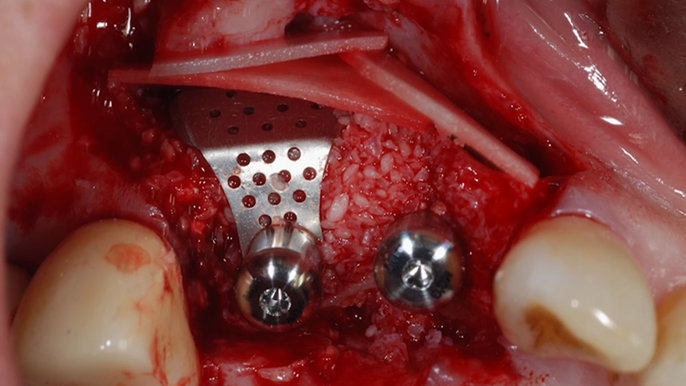

Clinical case: R2GATE GUIDE surgery with GBR

- Courtesy of Dr. Kwang Bum Park, Korea -

Dr. Kwang Bum Park, digital guided surgery, bone regeneration, maxillary posterior, #13, #14, guided surgery, GBR, AnyRidge, i-GEN, Mega-Oss, R2GATE, R2GATE Full surgical kit